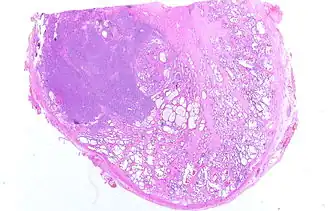

![]() Микрофотография инвазивной аденокарциномы простаты | |

Рак предста́тельной железы́ (рак проста́ты, карцино́ма проста́ты, карцино́ма предста́тельной железы́; англ. prostatic cancer, лат. adenocarcinoma prostatica) — злокачественное новообразование, возникающее из эпителия альвеолярно-клеточных элементов предстательной железы.